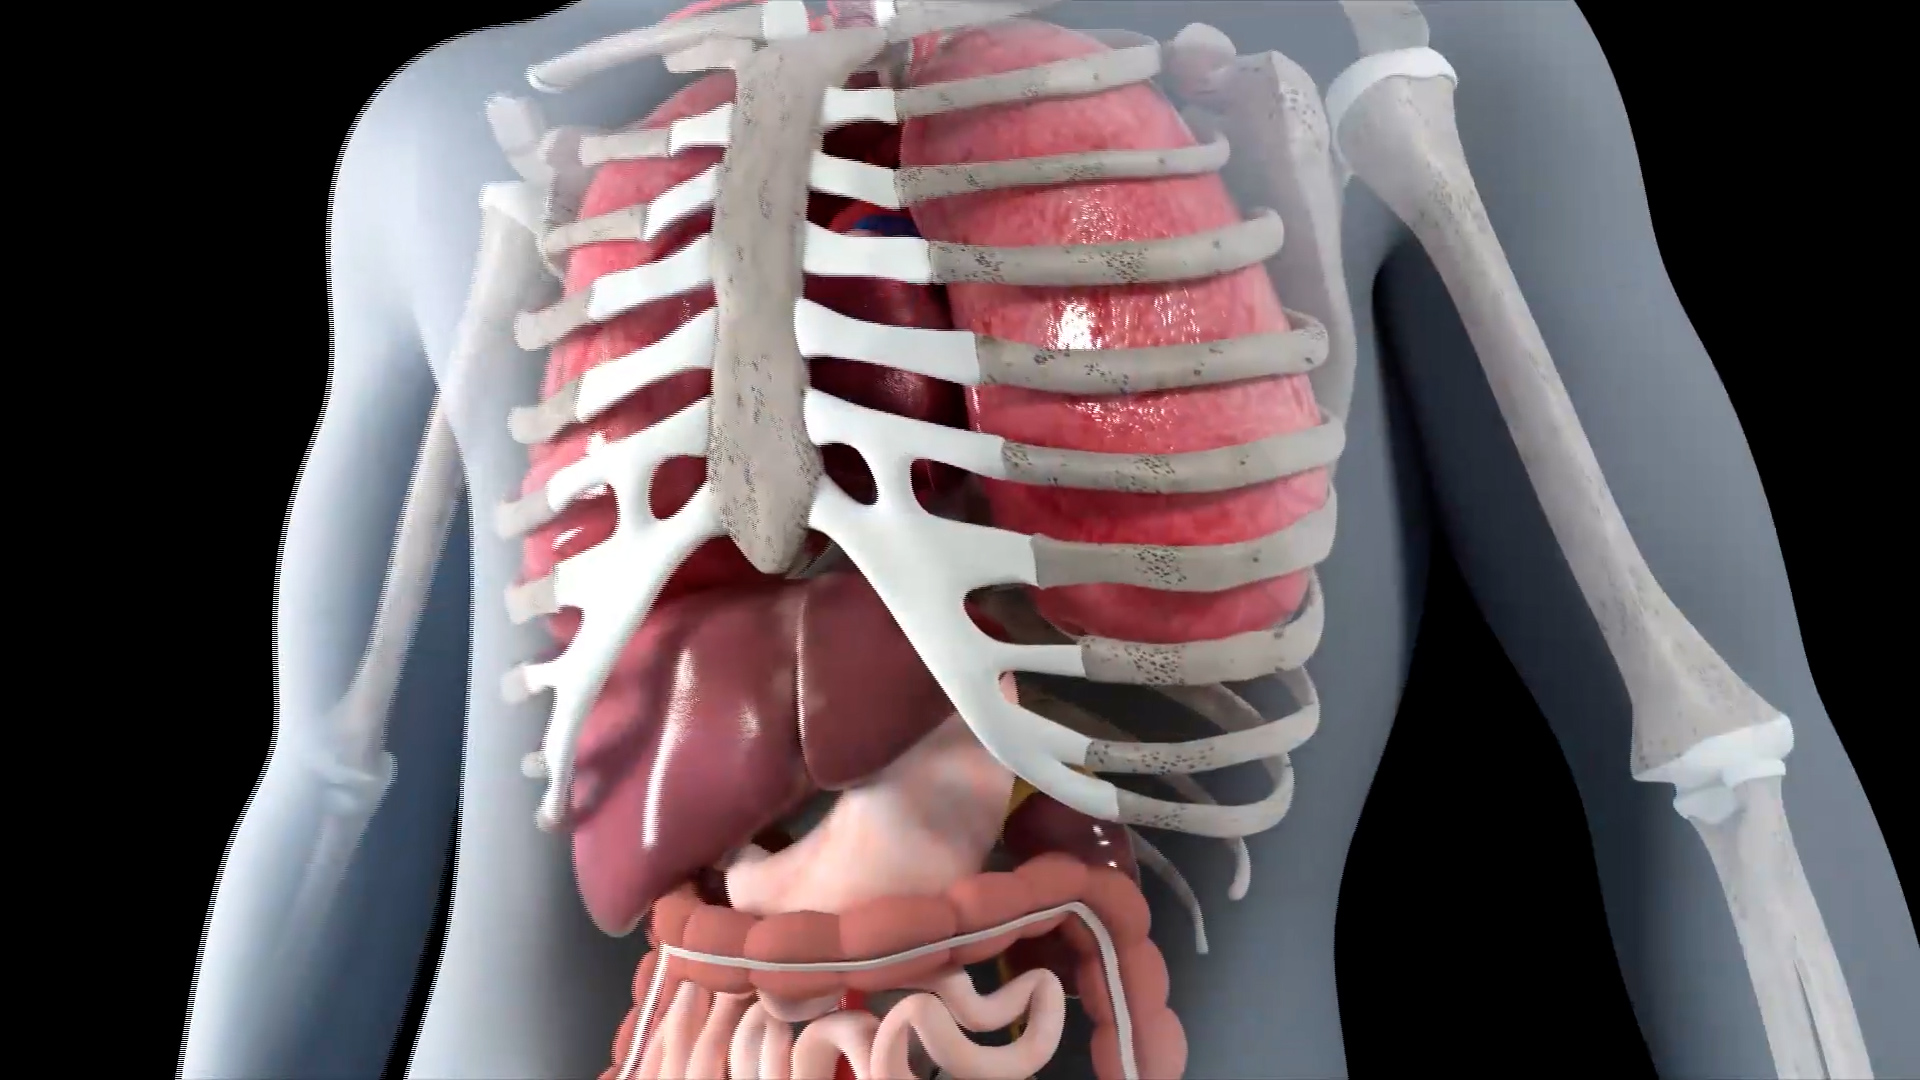

Θάνατοι από καρδιαγγειακά αίτια: μπορούν να προληφθούν με σωστή ενημέρωση – Εκπαιδευτική πλατφόρμα για γιατρούς

Οι θάνατοι από καρδιαγγειακά αίτια είναι η πιο συχνή μορφή θανάτου. Κάθε χρόνο σε παγκόσμιο επίπεδο 3 στους 10 ανθρώπους πεθαίνουν από νοσήματα που σχετίζονται με την καρδιά, με πιο συχνό το έμφραγμα και το εγκεφαλικό επεισόδιο. Το Αμερικανικό Κολλέγιο Καρδιολογίας έχει δημιουργήσει μία πλατφόρμα για την ενημέρωση των γιατρών σχετικά με την πρόληψη των μη μεταδοτικών νοσημάτων, όπως είναι η υπέρταση και ο διαβήτης που αποτελούν παράγοντες κινδύνου για την καρδιά. Στην πλατφόρμα έχουν ήδη εγγραφεί πολλοί Έλληνες γιατροί.